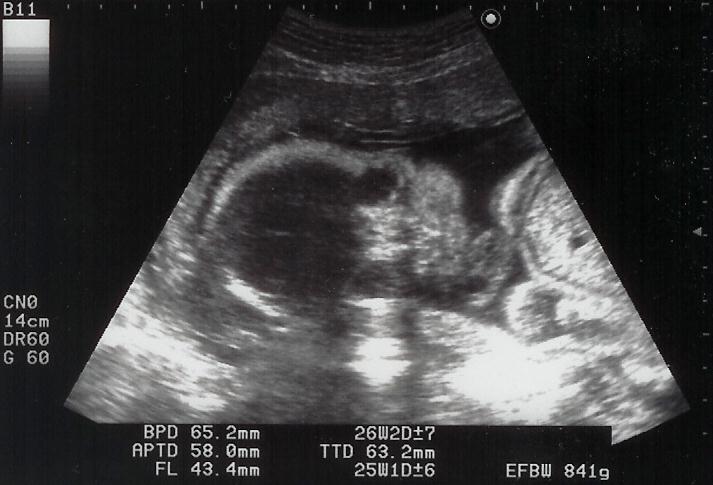

|  |  shigeru26週の健診です。shgieruは841gになりました。心音もしっかりしていて、元気・順調です。ママも今回は体重OK。でも、「塩分は控えめ」(高血圧気味)

と母子手帳に書かれてしまいました。